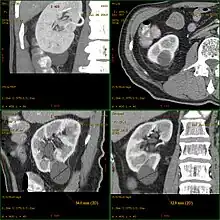

Kyste rénal

Un kyste rénal est une sorte de poche sur le rein contenant du liquide. Sa formation est assez fréquente en vieillissant. Les kystes sont souvent bénins (kyste simple) et ne nécessitent aucun traitement ou suivi particulier.

Dans certaines maladies rénales génétiques telles que la polykystose rénale type récessif (PKR) ou la polykystose rénale type dominant (PKD), du fait de l'abondance et de la grosseur des kystes, les reins polykystiques peuvent prendre un volume considérable. Le diagnostic repose principalement sur l'échographie qui révèle les kystes. Une échographie négative après l'âge de 30 ans permet d'éliminer le diagnostic de PKD.